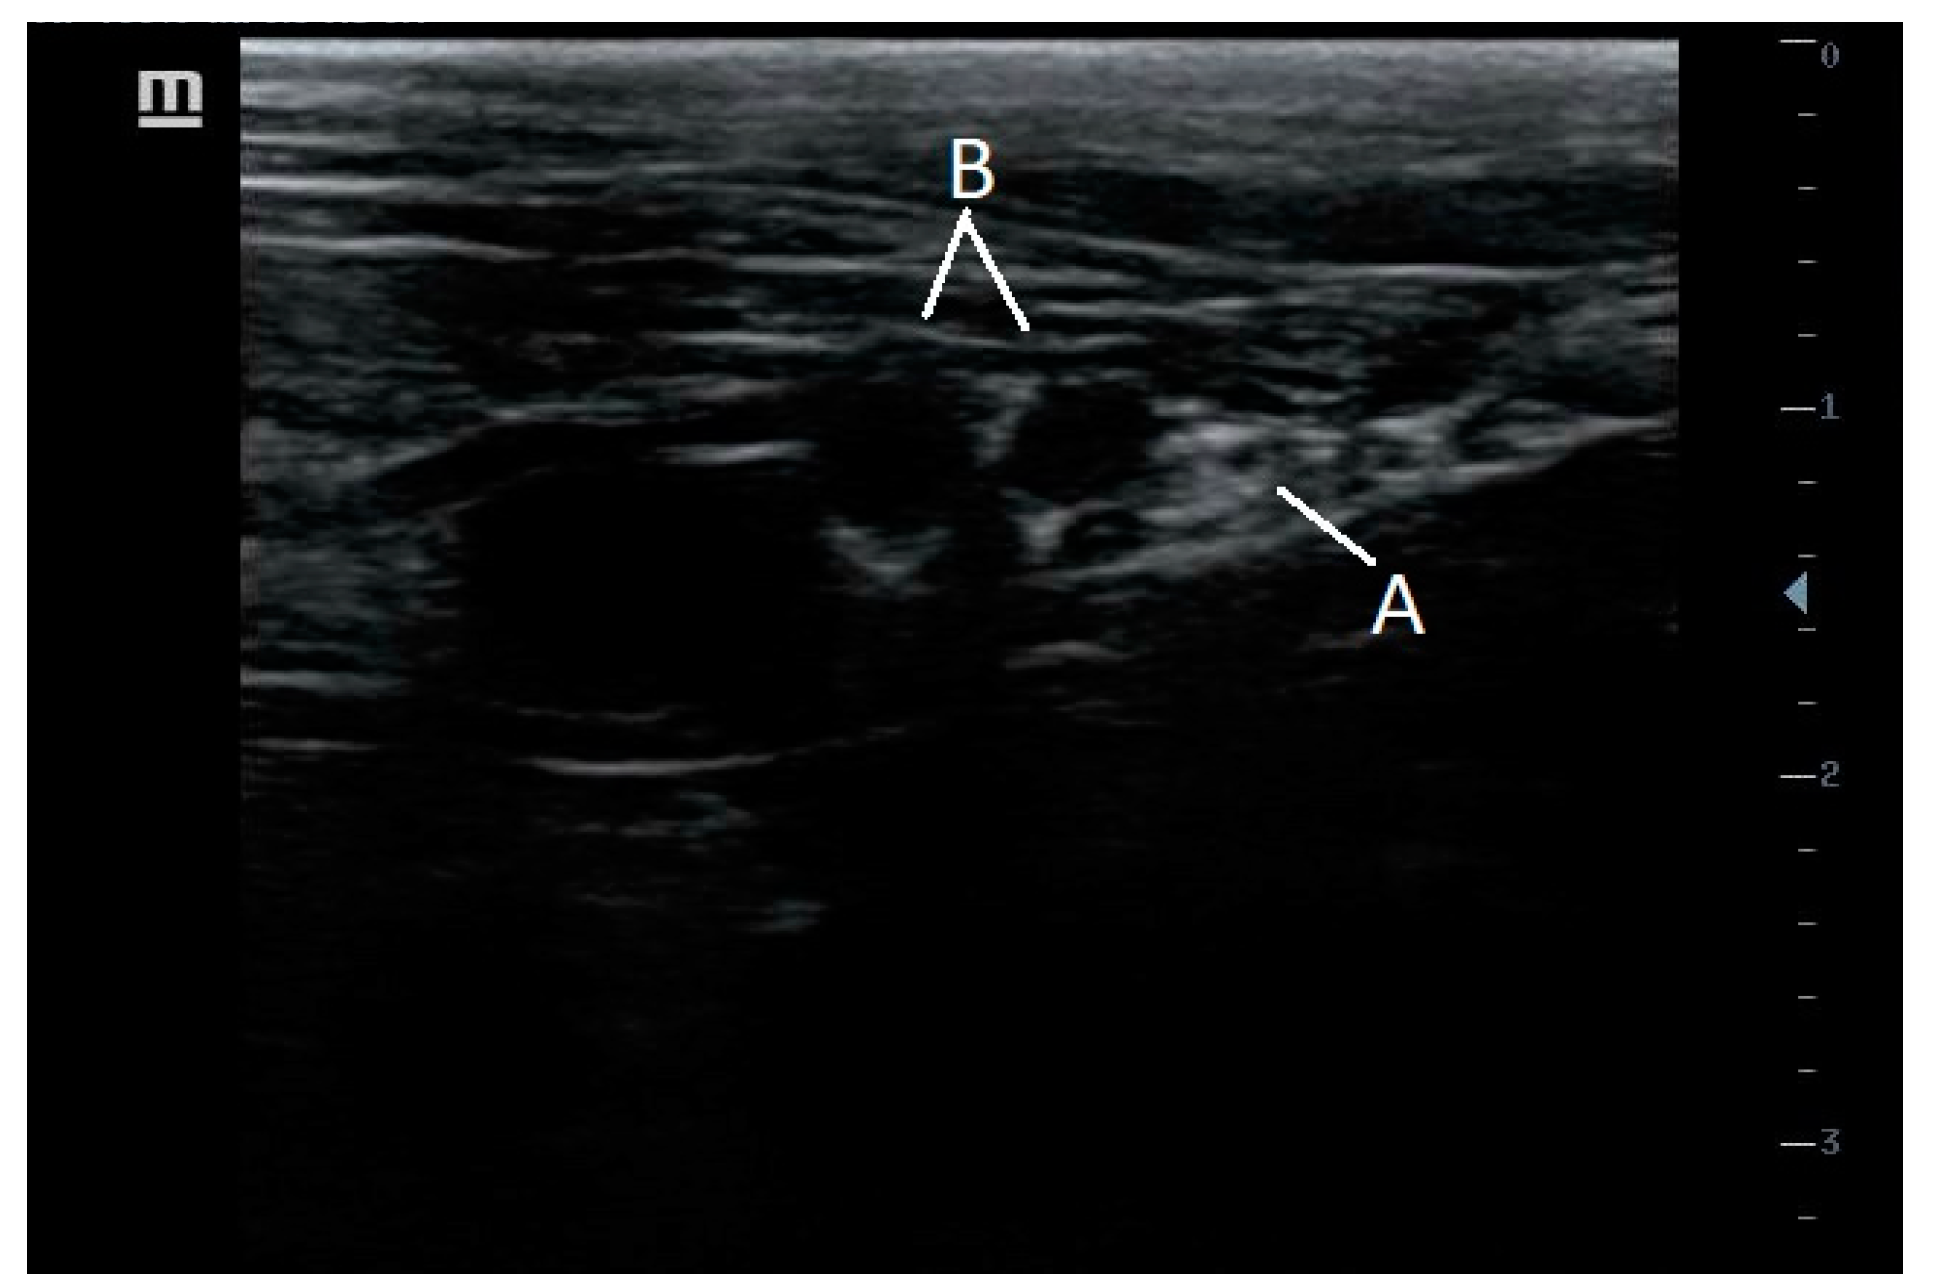

7.3. Radial, Ulnar, Median and Musculocutaneous Nerves Block (RUMM)